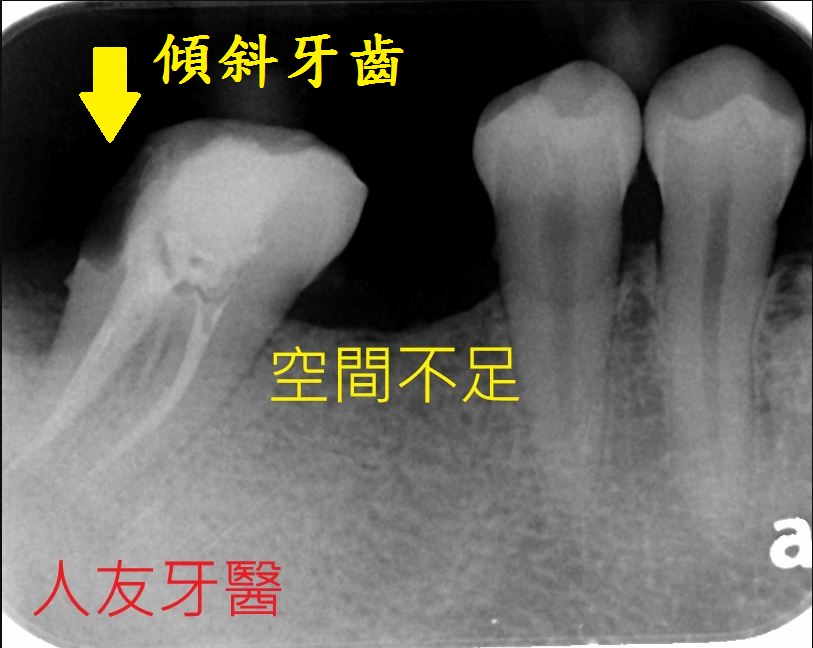

拔完牙後一個月,看傷口癒合情況,因兩顆門牙缺牙太久,齒槽骨流失比較多,醫師建議補骨跟植牙同時進行,植入三根牙根,位置分別在於右邊側門牙一顆,右邊正門牙和左邊側門牙。